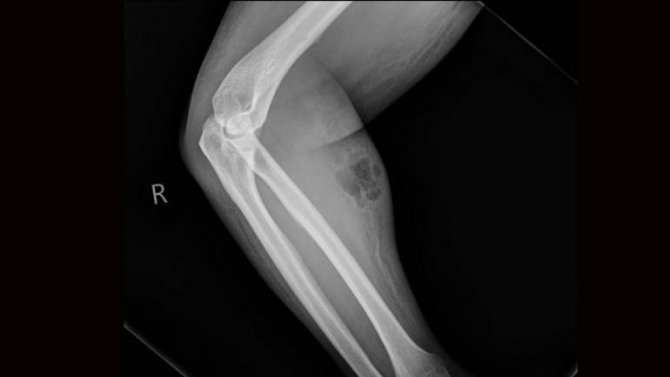

Doktorlar, hastanın ön kolunda ciddi şekilde şişlik ve kızarıklık olduğunu fark etti.

Yapılan tetkiklerde hastanın sırt ağrısını geçireceği düşüncesiyle 18 ay boyunca koluna kendi spermini enjekte ettiği ve deri altı yangısı rahatsızlığına yakalandığı ortaya çıktı.

İnternetten satın aldığı enjeksiyon iğnesi ile 18 ay boyunca ön koluna ayda bir doz sperm enjekte eden ve bu sayede sırt ağrılarından kurtulacağına inanan hastanın sırt ağrıları dinmek bilmedi.

Doktorların enjekte edilen spermi deri altından çıkarmak istediği ancak adamın tedavi olmadan hastaneden ayrıldığı belirtildi.